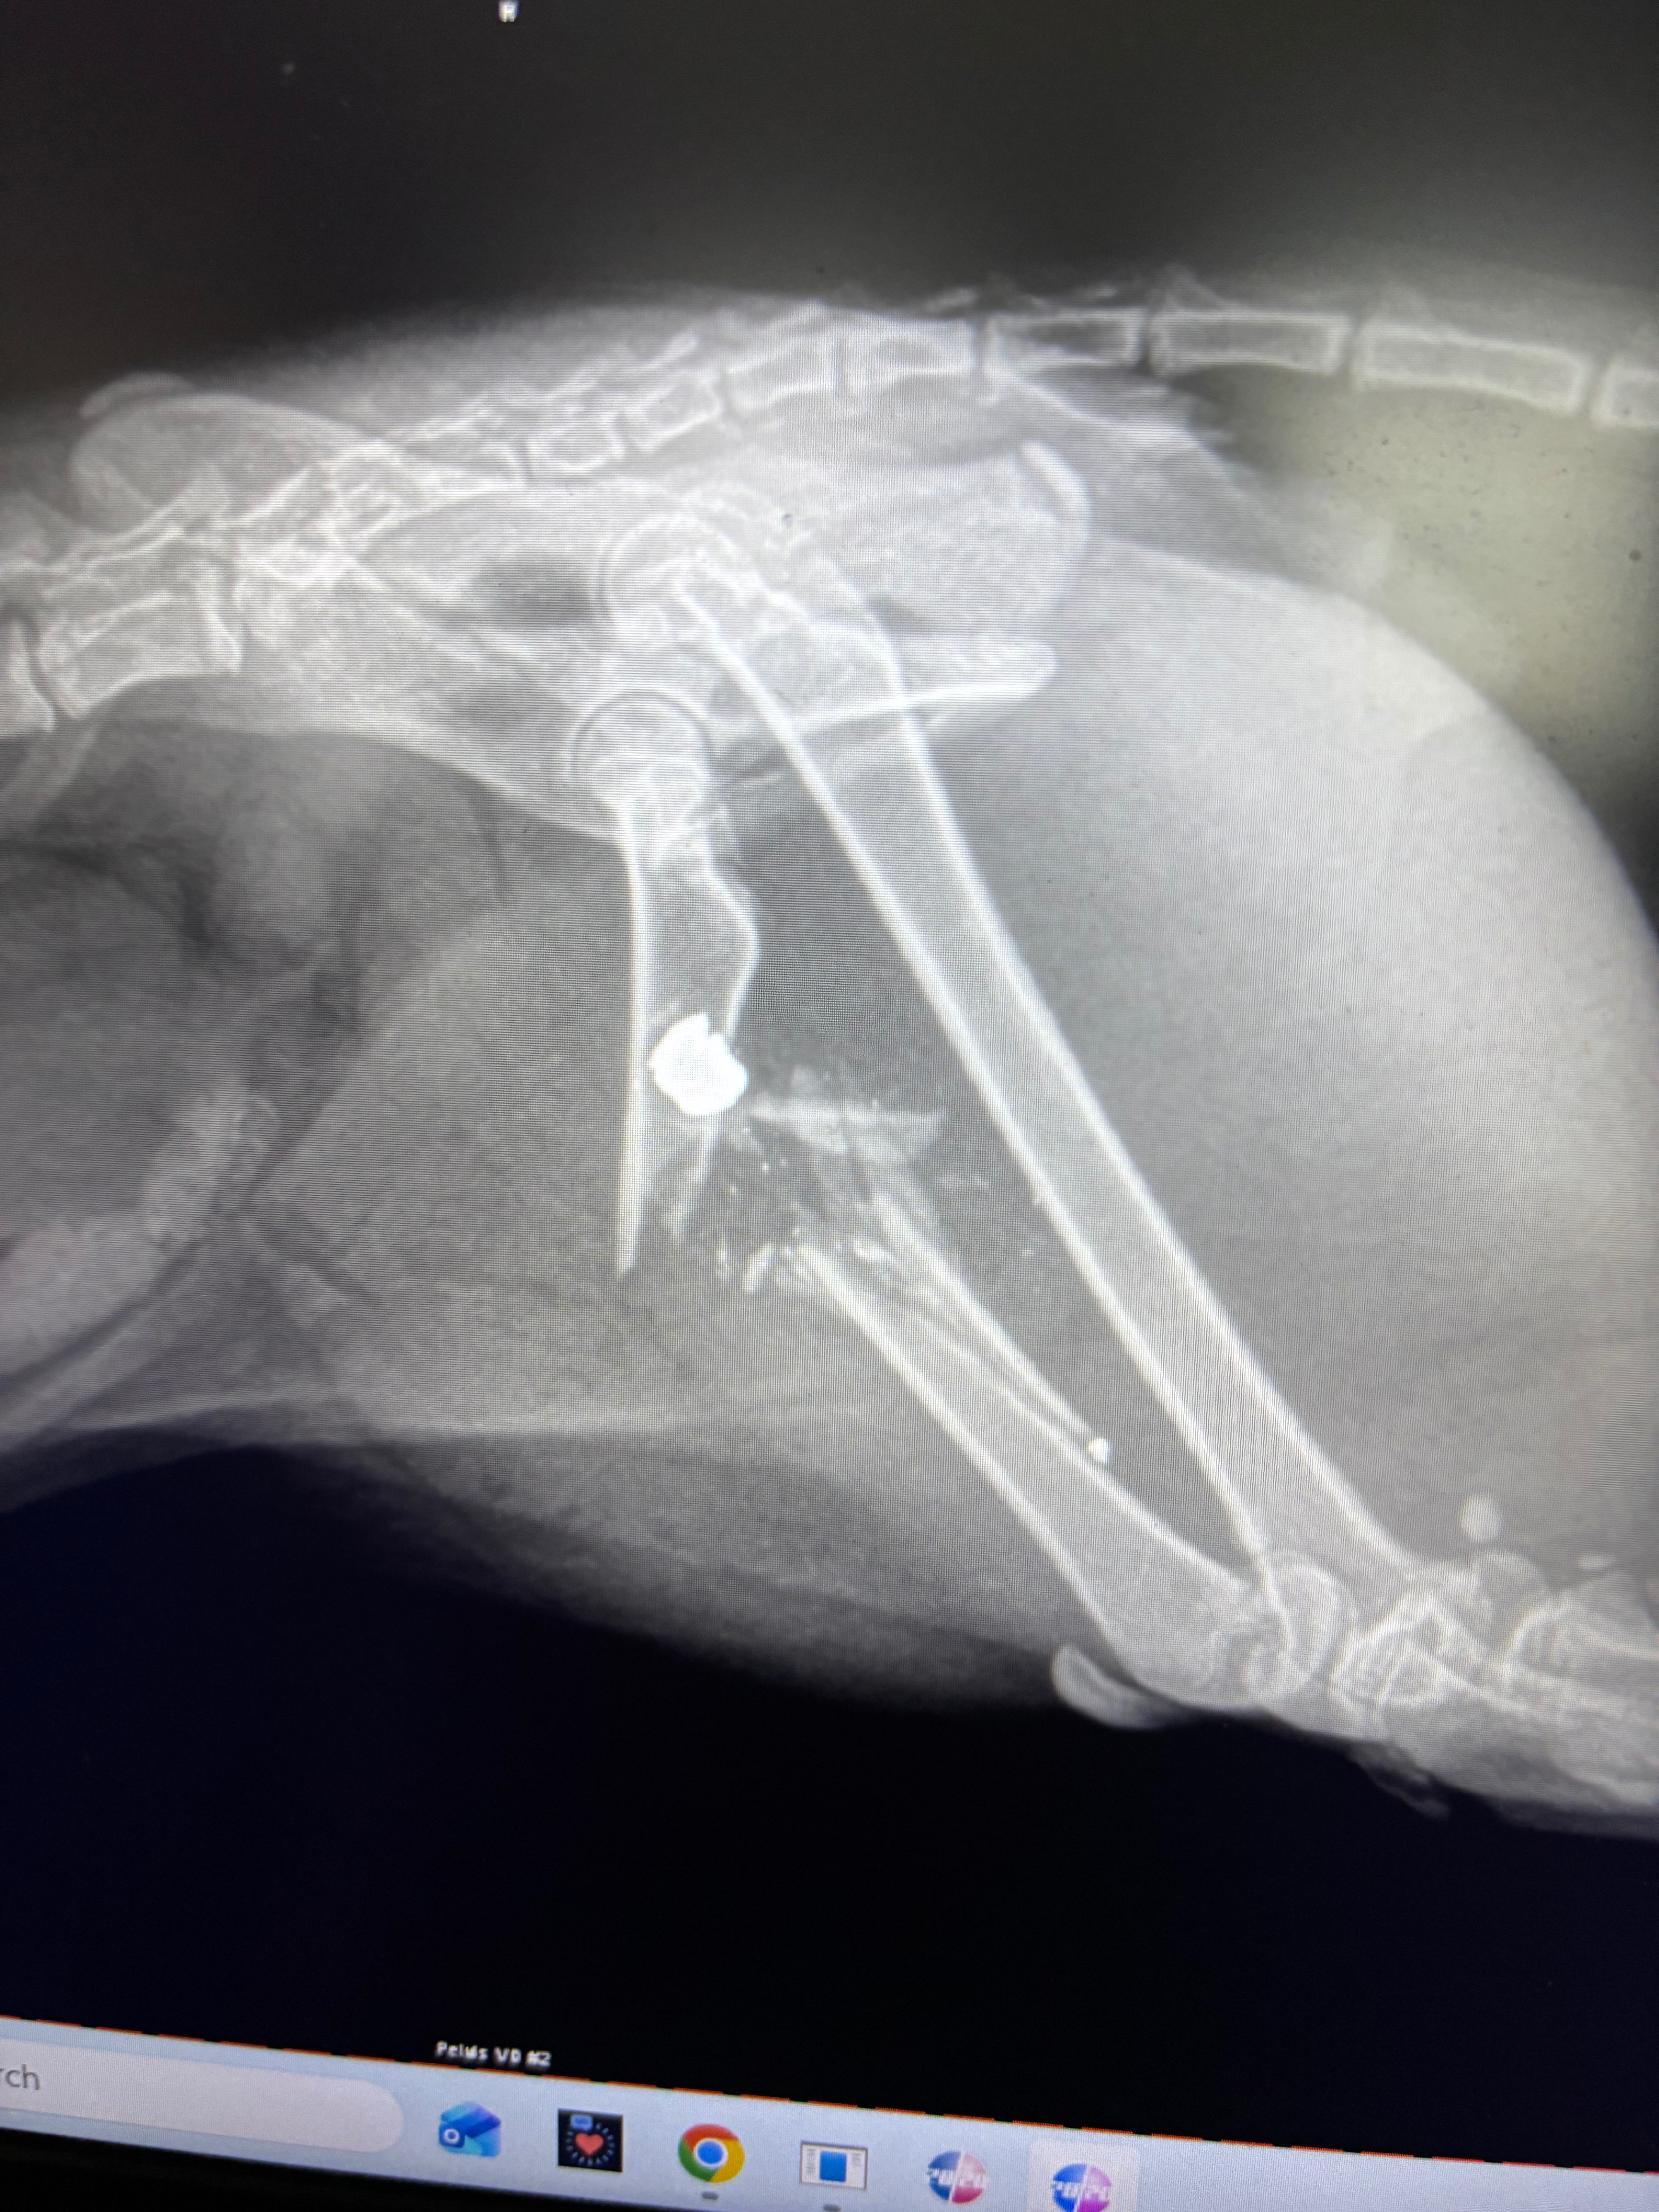

Mud is my beloved cat, and he means the world to me. Just two days ago, while he was outside in my backyard with me, someone shot him in the back leg. The injury is severe, and the only way to save his life is through amputation surgery. I am heartbroken and angry that someone could do this to an innocent animal, and I am struggling with the reality that I cannot afford the surgery he desperately needs.